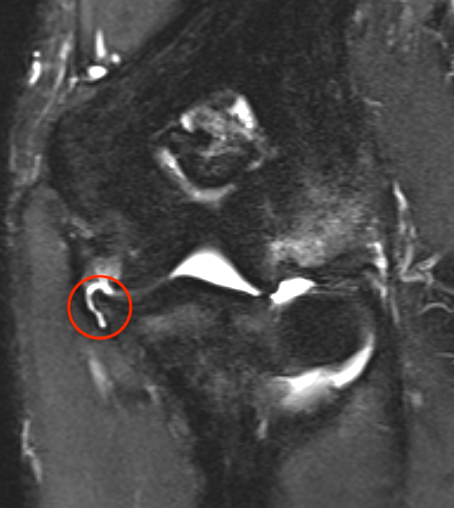

High grade partial distal UCL tear

PRLIPRLI

Bony avulsion UCL complex medial epicondyle

PRLIPLRI

Bony avulsion UCL sublime tubercle